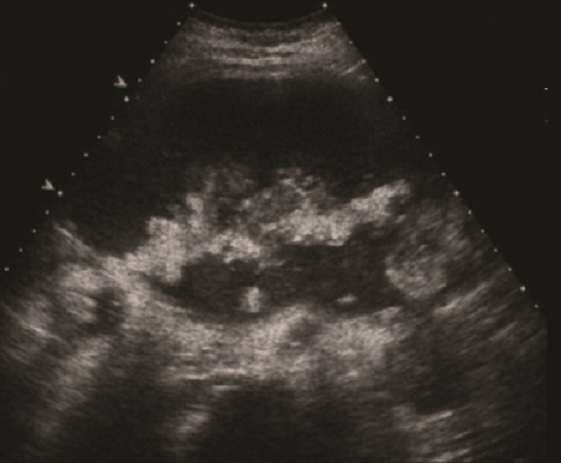

. Echographie :

Image echographique

percutanee direct de

pancreatite chronique est image de hyperechogene

heterogeneite de la

parenchyme pancreatique , sa taile peut augemente ,

normalement ou diminue sa bord est irregulier ,parfois

en presente des nodules calcification parenchymeteuse ou bien

image calcaire des calculs du canal pancreatique ce qui donne

de aspect de cone de l.ombre posterierure, en ce cas les

canal intra pancreatique sont dilates .

Les faux kyste associe peut en presente et se donne des images aechogene ou

hypoechogene intrapancreatique . Imge de ascite parfois se

en voyait